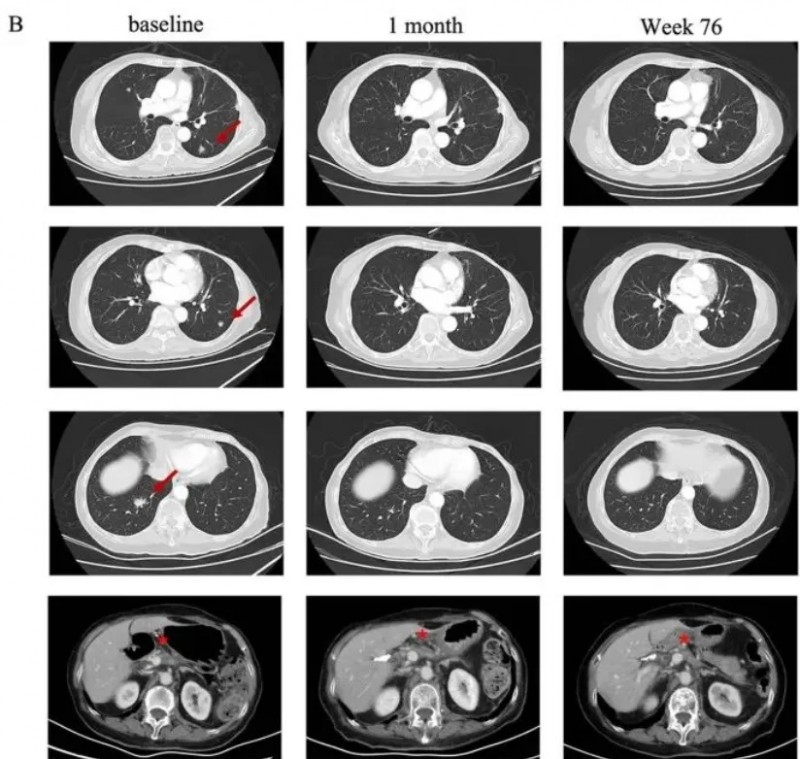

除了胃癌外,satri-cel(CT041)在治疗胰腺癌方面也展现除了振奋的疗效!《血液学与肿瘤学杂志》曾报道过一个典型案例:一名75岁胰腺癌患者,Claudin18.2表达为3+/60%,病理分期pT2N0,术后接受一线S-1单药化疗后出现肺转移,遂入组接受CT041回输治疗。

结果令人振奋:依据RECISTv1.1标准,患者在CT041输注后第4周即达部分缓解(PR),后续肺部转移病灶完全消失,实现完全缓解(CR)。截至2023年7月末次随访时,患者仍持续维持缓解状态,凸显satri-cel在胰腺癌治疗中显著的抗肿瘤活性与持久疗效。

▼该患者CT041治疗前后肺部病变的放射学评估

▲图源“J Hematol Oncol”,版权归原作者所有,如无意中侵犯了知识产权,请联系我们删除